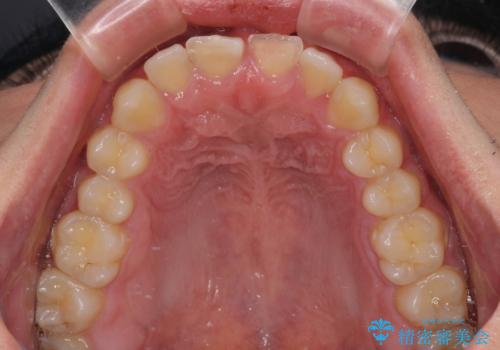

- 酔っ払って転んだらしく、目が覚めたら病室で歯が欠けていたとのことで来院された患者様です。

痛みを感じており、歯の欠けている状況から、神経組織のダメージも想定されました。

無菌的環境下にて歯の状態を調べ、最終的にオールセラミッククラウンにて補綴治療を行うこととしました。

幸いにも神経組織に影響はなく、健全な状態で治療を終えることができました。

歯肉の腫脹が目立っていたため、衛生指導も並行して行い、引き締まった歯肉になりました。